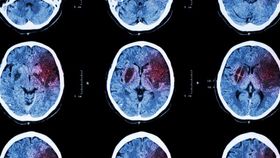

When people have a stroke, time is everything. During these events, regions of the brain are starved of oxygen, and the cells consequently begin to die. The longer it takes to get treatment, the more extensive the brain damage. But scientists have also discovered that there is a window directly after a stroke when people are able to relearn skills that might have been lost as a result of the condition. In addition, scientists have found that with mice they are able to “reopen” this window, by giving them a second stroke in the same region as the first. The results, however, cannot be applied to humans due to obvious ethical reasons.

The rest of this article is behind a paywall. Please sign in or subscribe to access the full content.To start with, mice were trained to complete a task that involved reaching through a small gap in their cage to grasp a piece of food. This behavior was very unnatural for the mice, but after spending 10 days in training, the rodents were able to successfully reach the food around half the time they tried. The researchers then induced a stroke within the motor cortex of the brain – the region responsible for voluntary movement – which prevented the rodents from being able to perform the task at all. After waiting a week, past the period of time during which scientists think the brain can recover following a stroke, the scientists tried to reteach the mice how to perform the task.

They found that the success rate for the rodents had fallen, with the mice now only successfully grasping the food around 30 percent of the time. The scientists then wanted to test whether this window of recovery could be reopened, and decided to do so by inducing a second stroke in the mice. For half the animals, they caused the stroke to occur again in the motor cortex, but for a control group they induced it in the visual cortex, far away from the site of the original stroke. Immediately following this, the researchers then taught the mice how to perform the task again.

For the mice that were given the second stroke in the motor cortex, the researchers found that the rodents were able to perform the grasping task as well as they could originally, regaining their 50 percent success rate. But for those that were given the stroke in the visual cortex, the mice never improved in their ability to complete the task. The study is published in the journal Neurorehabilitation & Neural Repair.

This, the researchers claim, suggests that the motor cortex is the only part of the brain that can be reopened in order to regain motor skills following a stroke, although exactly why this is remains unclear. While inducing the mice to have a second stroke appeared to achieve this, allowing them to be retaught previous skills, the scientists are aware that this technique would never be allowed on humans. What it does show, however, is that there is a lot more plasticity within the mammalian brain, and that it could lead to other ways to either reopen this window of recovery in humans or extend it to allow for greater time for recovery.

“If we can better understand how to reopen or extend the optimal recovery period after a stroke, then we might indeed change how we treat patients for the better,” Steven Zeiler, assistant professor of neurology at the Johns Hopkins University School of Medicine, said in a statement. “Our study adds new strong and convincing evidence that there is a sensitive period following stroke where it’s easiest to relearn motor movements – a topic that is still debated among stroke researchers.”